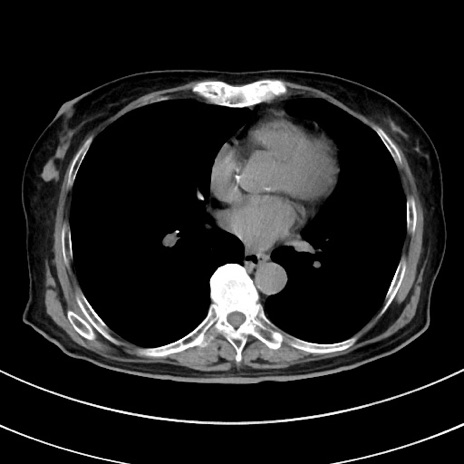

症例33(横断像)

【症例】70歳代 女性

【主訴】心窩部痛

【現病歴】延髄病変の精査・加療にて神経内科入院中。本日より心窩部痛あり。

【既往歴】虫垂炎

【身体所見】右下腹部を中心に圧痛と反跳痛あり。

【データ】WBC 10900、CRP 0.02